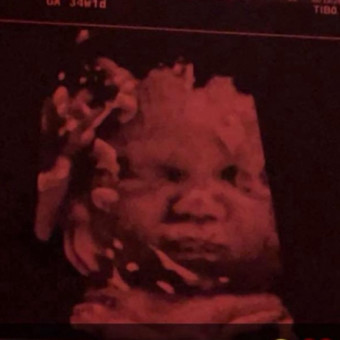

Baby MJ’s Registry💙

Anna Rodriguez & John Robinson